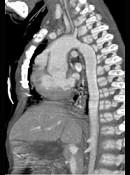

问题 患者,男性,8岁,发绀、气促,易感冒,彩超提示只见一个心室,CT检查如图所示,请选择正确的选项 ( )

选项 A、最常并发肺动脉瓣及瓣下畸形 B、可伴有内脏心房异位、房间隔缺损、共同心房、双上腔静脉等发育畸形 C、为一种较为复杂的先天性疾病 D、以前诊断主要依靠心血管造影 E、考虑为单心室共同动脉干

答案 ABCDE